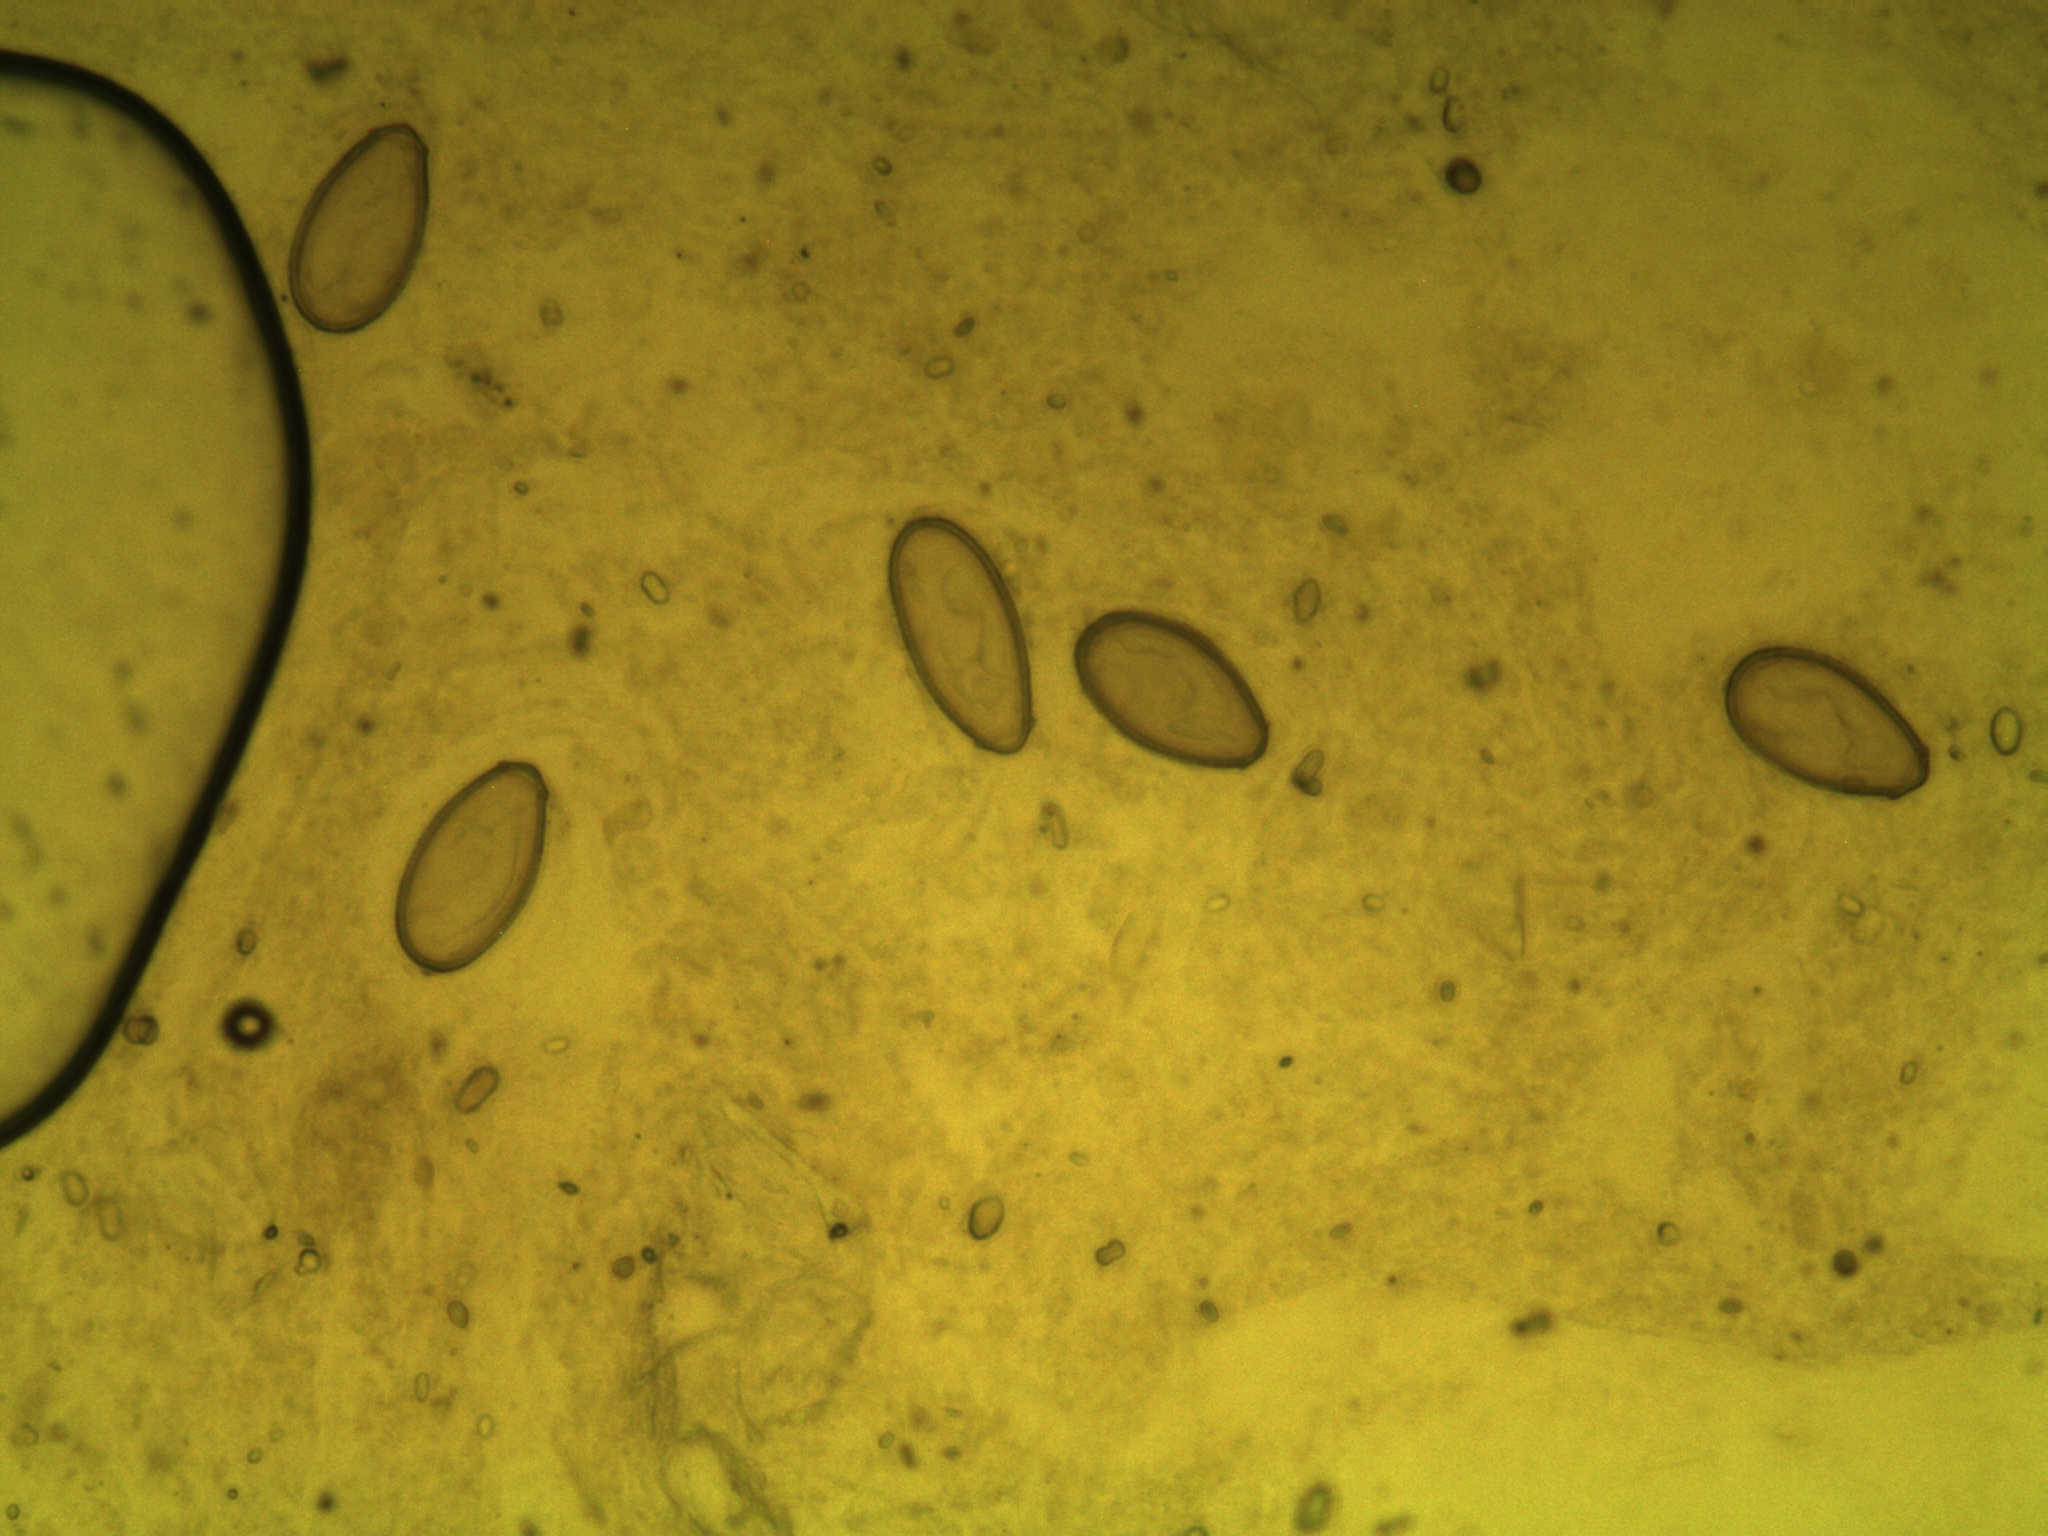

病犬常呈慢性经过,表现长期消化不良,异嗜,食欲减退,前期便秘,后期腹泻,间歇便秘或下痢交替出现,渐进性消瘦,可视粘膜苍白黄染;病的后期出现腹水,腹围膨大,扣诊呈水平浊音,上界随着体位的变化而变化,腹腔穿刺后有透明液体流出;病犬常呈站立姿势或犬坐姿势,呼吸困难,有的可触摸到肝脏肿大;实验室检查常见贫血、总胆红素、碱性磷酸酶升高;粪便镜检可确诊如图: